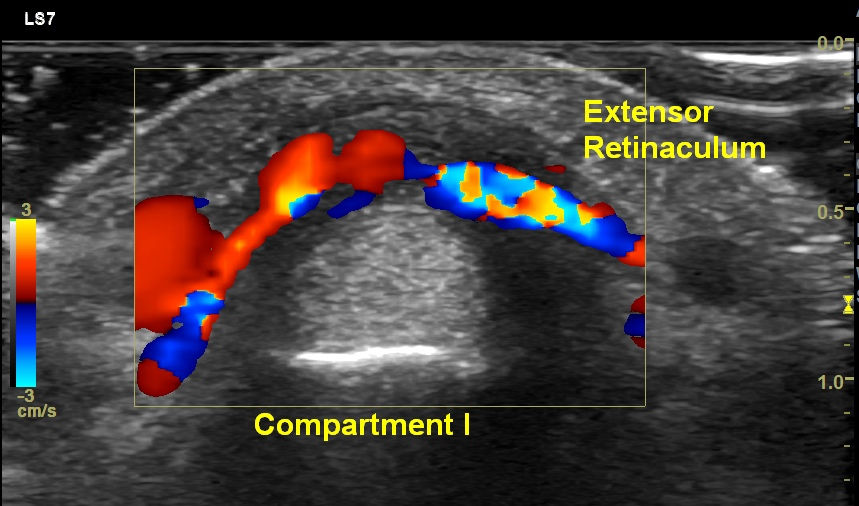

Ultrasound (US) imaging shows diffuse thickening of the extensor retinaculum over abductor pollicis longus (APL) and extensor pollicis brevis (EPB) tendons. Mild effusion with synovial hypertrophy is seen in the APL & EPB tendon sheath. Power Doppler shows increased vascularity in the thickened synovium. Dynamic imaging shows restricted gliding of APL & EPB tendons below the thickened extensor retinaculum. Based on the clinical presentation & imaging findings, a diagnosis De Quervain’s tenosynovitis was made.